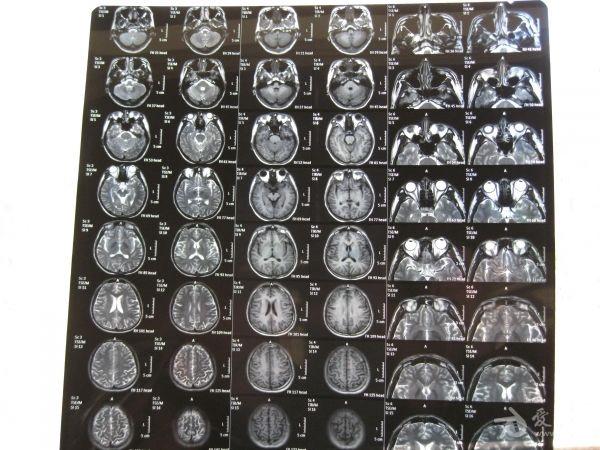

帮忙看一下头颅MRI

脑外伤后近两年,一直感觉不适,行MRI检查。

将头颅平扫+头颅增强+眼眶平扫+眼眶增强的MRI拍照后发上来了,请大家帮忙阅片。看一下是否有颅内软化灶、眼部病变及颈动脉海绵窦瘘CCF表现?另外,帮忙看一下上鼻道及筛窦内线样长T2信号影为何物?是不是脑脊液鼻漏?(影像报告上说不排外脑脊液鼻漏可能)。